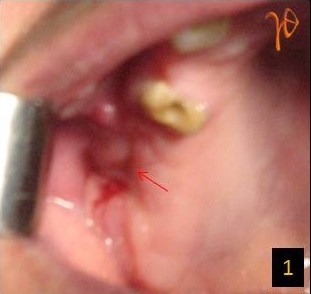

Μετεξακτική λοίμωξη(Εικ.1) μετά από εξαγωγή του #17, μη ανταποκρινόμενη στη συντηρητική αγωγή. Μετά από πανοραμική ακτινογραφία(Εικ.2) και καλλιέργεια, θετική για Β-στρεπτόκκοκκο(ομάδα C κατά Lancefield), έγινε τοπική απόξεση και συρραφή με την ενδεικνυόμενη αντιβιοτική κάλυψη. Η λοίμωξη δεν υποχώρησε και με την υπολογιστική τομογραφία(Εικ.3 και 4) επιβεβαιώθηκε η κλινική υποψία στοματοκολπκής επικοινωνίας και οδοντογενούς ιγμορείτιδας.

Εικ. 1: Μετεξακτική λοίμωξη στην άνω δεξιά γομφιακή περιοχή (βέλος).